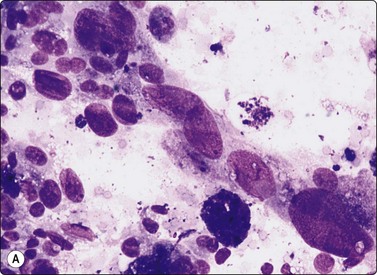

image image

Fig. 6.18 Follicular neoplasm

Cellular smears of single cells, microfollicles or rosettes in a repetitive manner; benign adenoma by histology (A, MGG, HP; B, Pap, HP).

Fig. 6.19 Follicular neoplasm

Smears very similar to Figure 6.18; follicular carcinoma with vascular invasion by histology (A, MGG, HP; B, Pap, HP).

Smears in FN are cellular in a bloody background that is usually devoid of colloid. Many uniform-sized follicular cell clusters, microfollicles and rosette formations are present. Syncytial aggregates, nuclear crowding and overlapping are also often seen.

The repetitive smear pattern with uniform cell population is in contrast to the variable pattern of different cell types seen in colloid and hyperplastic nodules. Microacinar clusters with a central lumen (that may contain a drop of colloid) represent microfollicles (Figs 6.18, 6.19 and 6.21B). These are characteristic of FN but may be found focally in NG. Rosette-like groupings without a lumen (Fig. 6.20) suggest a more solid growth pattern. A trabecular pattern is represented by rows and elongated aggregates of epithelial cells that resemble papillary structures when they adhere to strands of vascular stroma (see Fig. 6.33B,C). Small blood vessels with adherent epithelial cells can be found in any type of follicular neoplasm (see Fig. 6.25A).